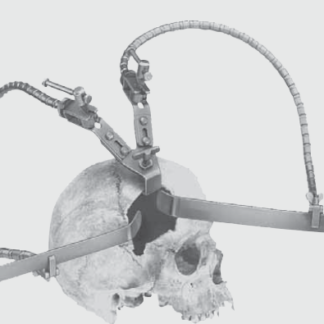

FF262R ~ HIRNSPATELHALTER YASARGIL DOPP.END. ~

selbsthaltender Hirnspatelhalter nach YASARGIL, doppelendig

bestehend aus:

FF268R Grundkörper zur Aufnahme von zwei flexiblen Armen

FF270R 2 flexible Arme

FF273R 2 Halter für flache Hirnspatel